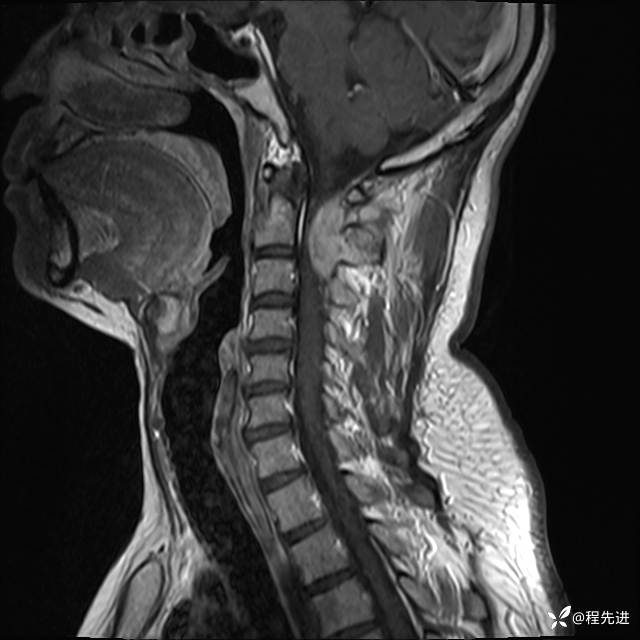

MRI平扫+增强:

T2: